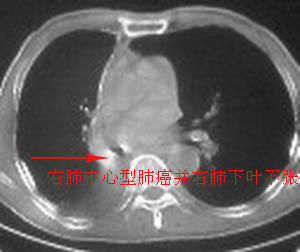

右肺下叶支气管阻塞,右下叶不张,考虑中心型肺癌伴下叶不张

先考虑:右下肺中心型肺癌伴下叶肺不张、胸腔积液

右肺下叶支气管闭塞,中间段支气管狭窄,下叶不张,胸腔及叶间积液.中心型肺癌伴下叶肺不张.胸腔和叶间积液.

考虑中心型肺癌伴下叶不张

考虑:右下肺中心型肺癌伴下叶肺不张、胸腔积液

考虑中心型肺癌伴下叶不张,肺底积液吧。

考虑右下肺中心型肺癌伴下叶肺不张、胸腔积液。